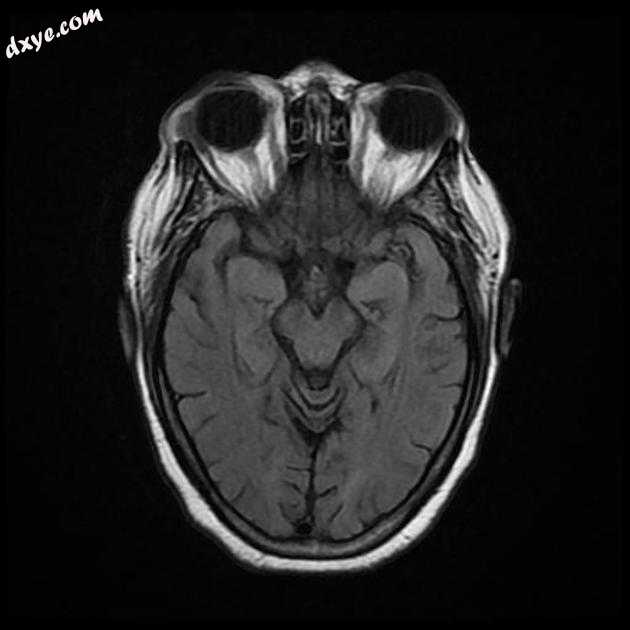

Axial T1

Axial FLAIR

MRI 序列显示左侧大脑中动脉 (MCA) 区域分布中的弥散受限区域,在 FLAIR 序列上不可见。在 GE 序列上没有看到出血性转化。 MRA 3D-TOF 显示左侧大脑中动脉完全闭塞。

早期超急性大脑中动脉 (MCA) 区域梗死的 MRI 特征。